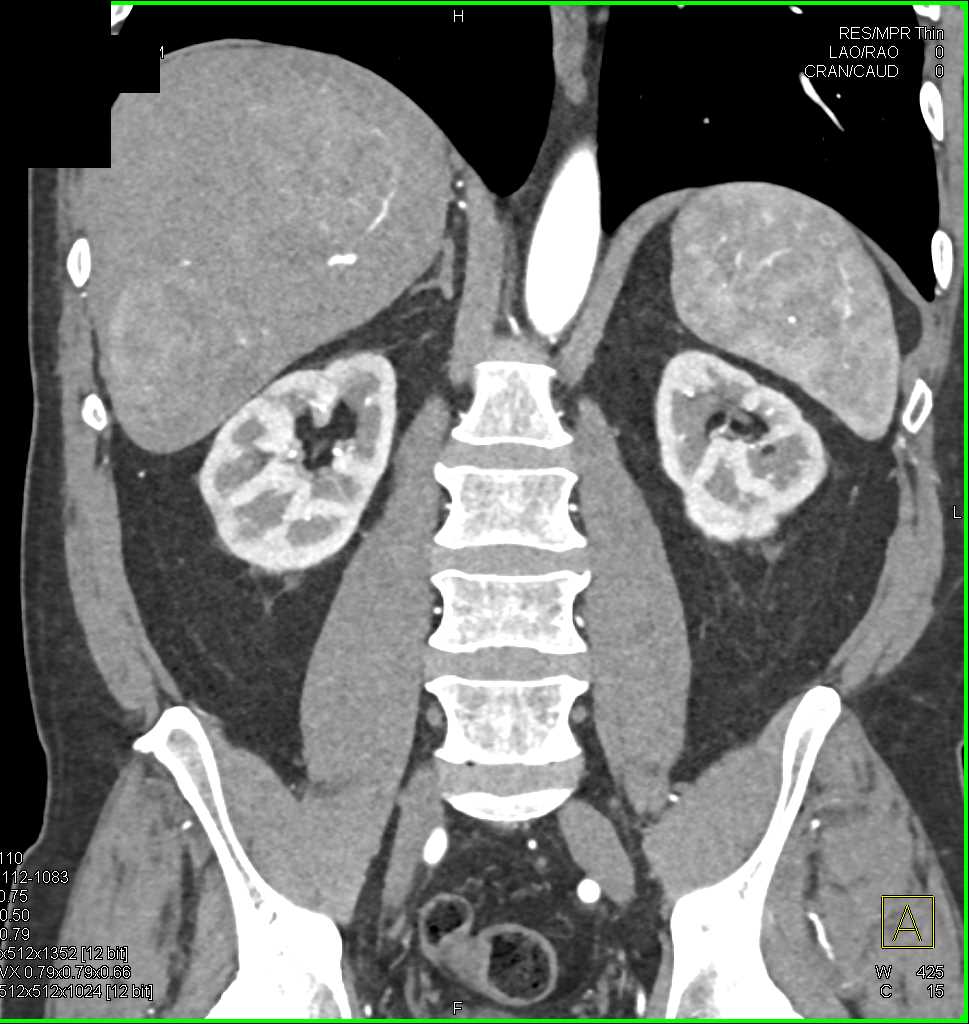

Carcinoid Tumor with Desmoplastic Reaction